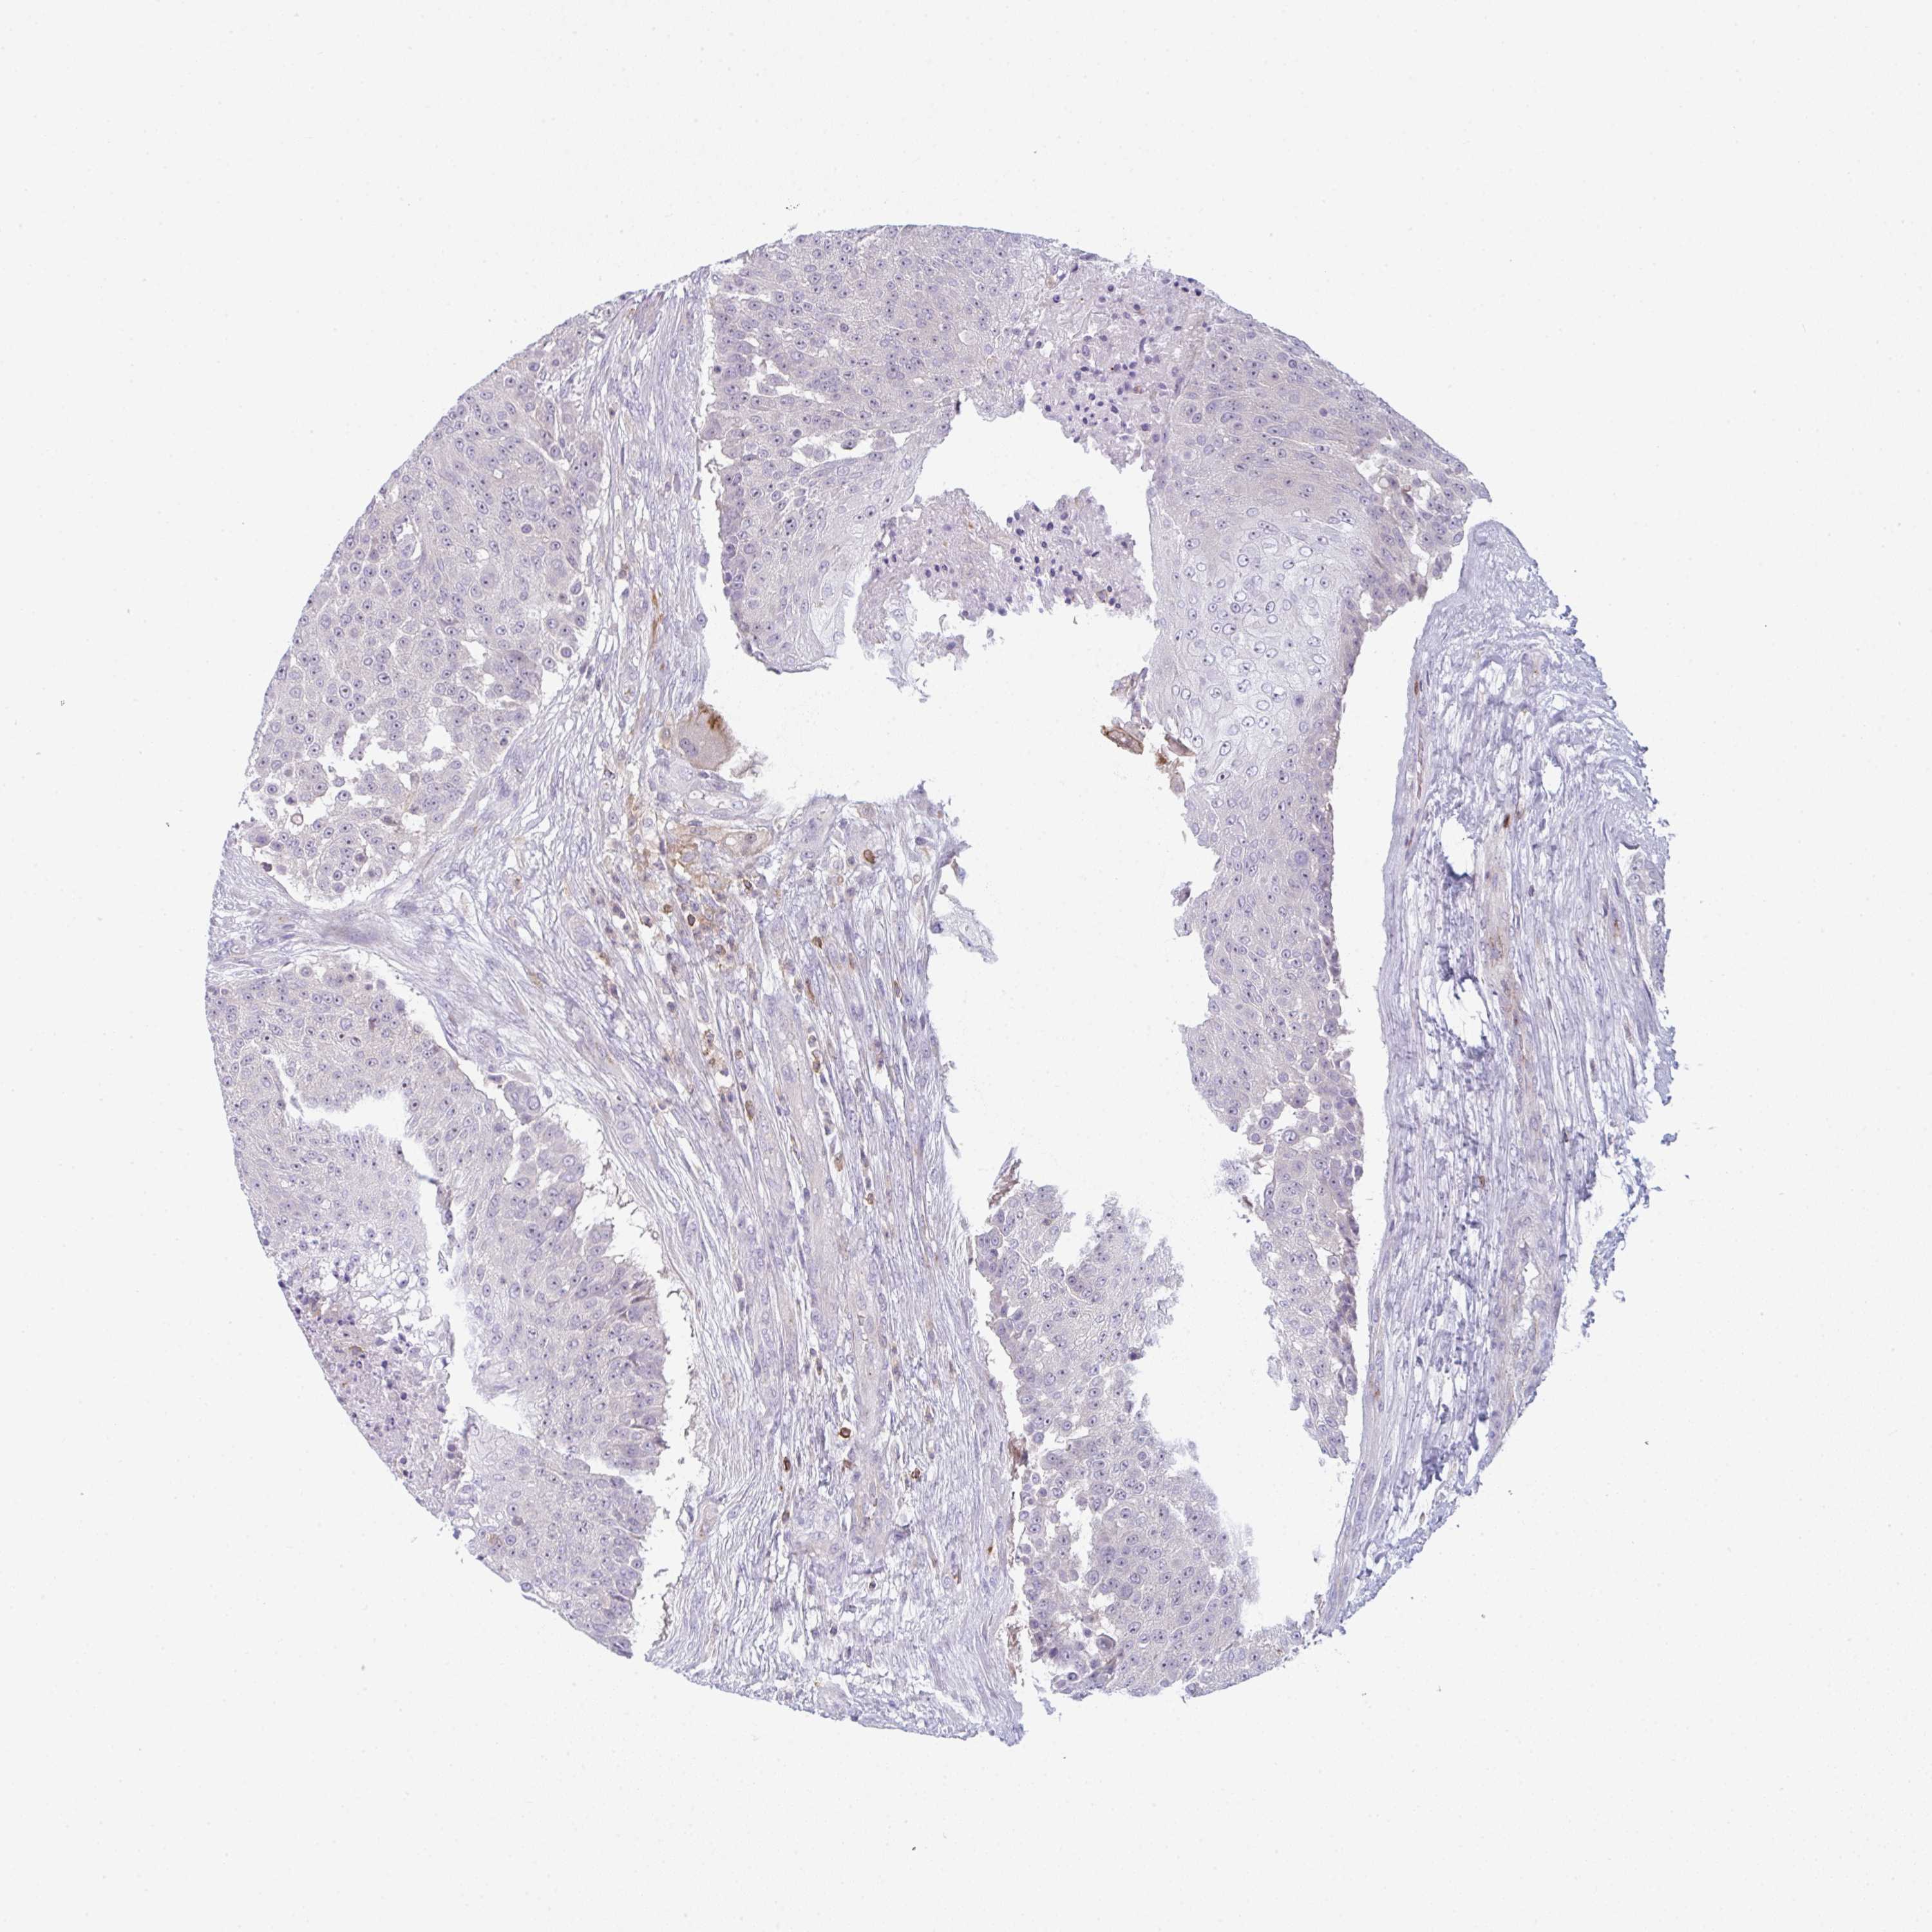

UROTHELIAL CANCER - Protein expressioni

A mouse-over function shows sample information and annotation data. Click on an image to view it in a full screen mode. Samples can be filtered based on level of antibody staining by selecting one or several of the following categories: high, medium, low and not detected. The assay and annotation is described here.

Antibody stainingi

Antibody staining in the annotated cell types in the current human tissue is reported as not detected, low, medium, or high, based on conventional immunohistochemistry profiling in selected tissues. This score is based on the combination of the staining intensity and fraction of stained cells.

Each image is clickable and will lead to virtual microscopy that enables deeper exploration of all samples and also displays staining intensity scores, fraction scores and subcellular localization as well as patient and tissue information for each sample.

Antibody HPA050092

Antibody CAB025368

Urothelial carcinoma, High grade

Urothelial carcinoma, Low grade